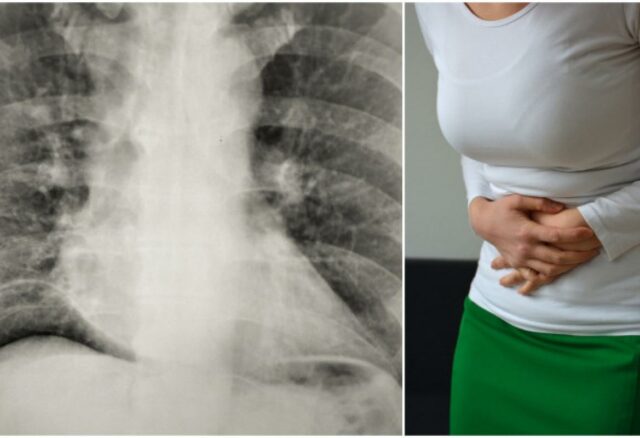

Jedna 24-godišnjakinja pojavila se na Hitnom odjelu Sveučilišta Stanford u Kaliforniji nakon što je doživjela jake bolove u trbuhu i prsima, koji su trajali šest sati. Njezina je bol bila oštra i pomaknula se iz donjega desnog dijela trbuha prema gore i proširila. Osim boli, koja se pojačavala dok se kretala, nije imala drugih simptoma.

Međutim, istu je stvar doživjela i nekoliko puta prije, šest i 12 mjeseci prije ovoga određenog posjeta. Daljnjim pregledom rendgenskim zrakama rezultat je uvijek bio isti: otkriven joj je zrak u trbušnoj (peritonealnoj) šupljini, stanje poznato kao pneumoperitoneum, piše IFL Science.

Pneumoperitoneum može biti uzrokovan bilo čime, od perforiranog čira do raka crijeva. Oni mogu izazvati zračne embolije, gdje se mjehurići zarobljavaju u krvnoj žili, blokirajući je, što zauzvrat može dovesti do smrti. Kao takvi, zahtijevaju hitnu istragu uzroka.